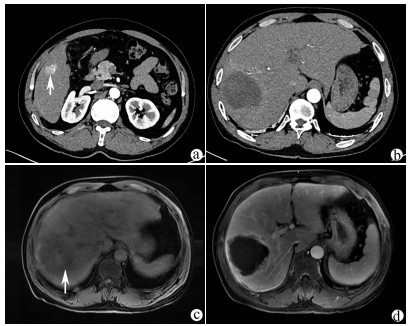

肝脏三维可视化重建技术在儿童复杂肝母细胞瘤肝切除术中的应用价值

赵頔, 叶进冬, 李华丽, 金奎, 刘翔, 李潇然, 段留新, 刘军桂, 吕伟, 段伟宏, 刘全达

2021, 37(9): 2130-2135. DOI: 10.3969/j.issn.1001-5256.2021.09.025

摘要(1330) HTML (406) PDF (3973KB)(67)

摘要:

目的  探讨肝脏三维可视化重建技术在儿童复杂肝母细胞瘤肝切除术中的应用价值。  方法  回顾分析2018年1月—2020年10月于火箭军特色医学中心实施了以根治性切除为目的的肝肿瘤切除术的30例肝母细胞瘤患儿的临床资料,根据术前是否行肝脏三维重建(IQQA-Liver系统)将所有患儿分为三维重建组(n=15)和对照组(n=15),比较2组患儿围手术期临床参数以及短期预后和随访情况。符合正态分布的计量资料2组间比较采用独立样本t检验,不符合正态分布的计量资料2组间比较采用Mann-whitney U检验。计数资料2组间比较采用Fisher确切概率法。  结果  三维重建组较对照组平均年龄更大[(55.7±10.2)月vs (28.2± 2.7)月]、POSTTEXT Ⅲ/Ⅵ期(12例vs 5例)和肝静脉或下腔静脉受累者(11例vs 3例)更多,差异均有统计学意义(P值均<0.05)。所有患儿均顺利完成手术,2组在出血量、手术时间、肝门阻断次数/时间、行肝段及部分肝切除例数方面,差异均无统计学意义(P值均>0.05)。术后中位随访时间9.5个月,三维重建组2例复发,分别于术后10个月和12个月确诊,目前继续化疗中;对照组4例复发,高于三维重建组(P=0.651),其中2例在术后7个月复发接受肝移植存活至今,另有2例复发后短期内死亡。  结论  三维可视化重建技术有助于更安全精准实施复杂儿童肝母细胞瘤肝切除术,尤其是可以使部分POSTTEXT Ⅲ/Ⅵ期患者安全实施扩大肝切除,从而避免行肝移植。